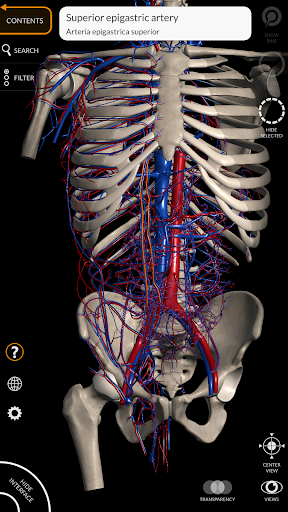

Các mô hình giải phẫu 3D đặc biệt chi tiết và có kết cấu lên đến độ phân giải 4k.

MÔ HÌNH GIẢI PHẪU 3D

• Hệ thống tim mạch

• Xoay và phóng to từng mô hình trong không gian 3D

• Tùy chọn ẩn hoặc cô lập một hoặc nhiều mô hình đã chọn

• Bộ lọc để ẩn hoặc hiển thị từng hệ thống

• Chức năng trong suốt